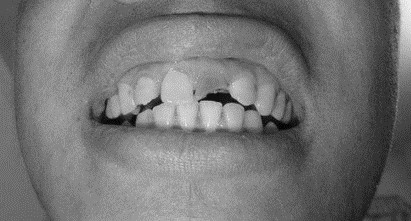

患者,男,38歲。上前牙變色1年,自述上前牙5年前受過外傷,唇側(cè)傾斜,檢查可見左上1牙冠變色,牙冠缺損近1/2,牙髓測試無反應(yīng),X線根尖片顯示患牙無明顯異常,全景片顯示雙側(cè)下頜智齒近中阻生,之前有發(fā)炎化膿病史,目前無咀嚼不適。口腔其余無異常。

檢查情況及X線片見下圖:

(1)下前牙變色1年,下前牙5年前受過外傷,唇傾明顯。

(2)檢查見左上1牙冠變色,牙髓測試無反應(yīng),牙冠缺損近1/2,X線片無明顯異常。